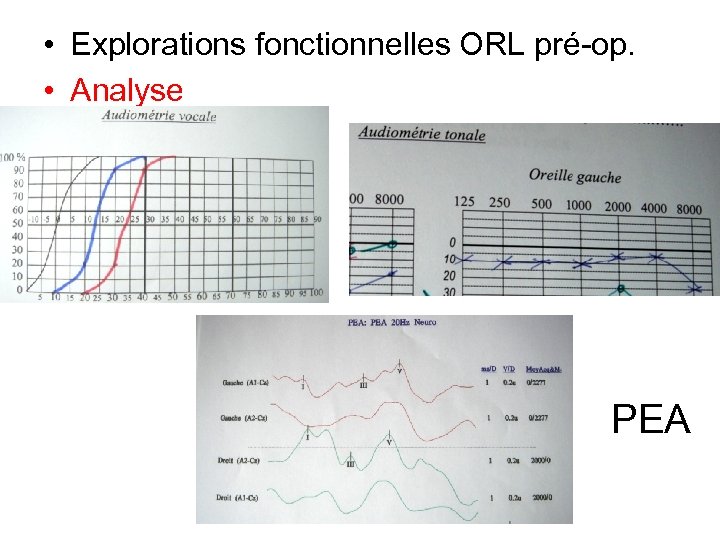

• Explorations fonctionnelles ORL pré-op. • Analyse PEA

• Explorations fonctionnelles ORL pré-op. • Analyse PEA